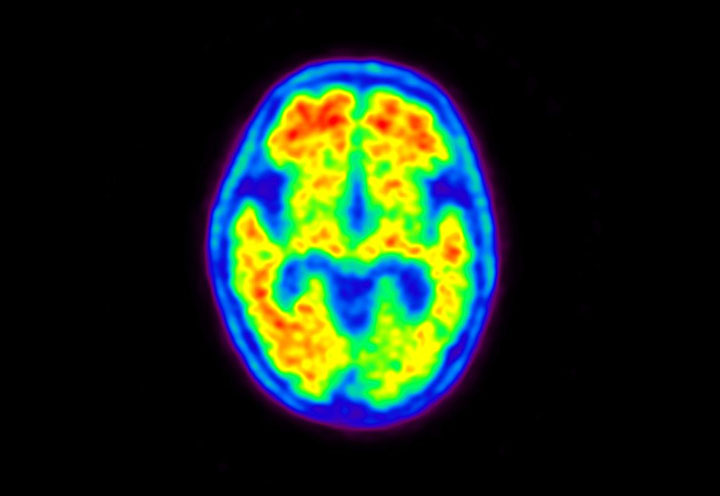

Head / Case5 : Amyloid

Courtesy : Kindai University Hospital

- Imaging protocol

- Injected dose: 4.27 MBq/kg, 18F-Flutemetamol

- Uptake time: 99 minutes

- Scan time: 20 minutes